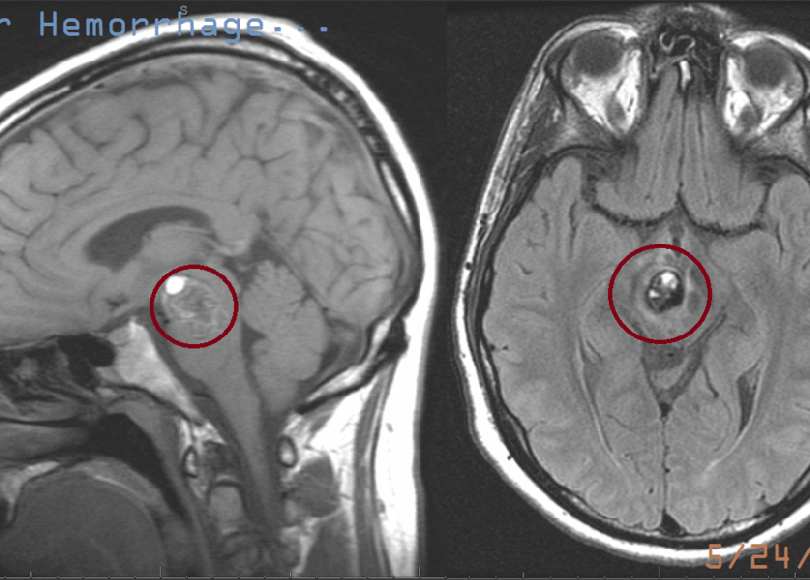

The images are labeled with the reason for and date of the scan. I’d only point out the first scan from May, 2009 showing a big blob of white stuff just below the very center of my brain profile and slightly off center looking at the top. It’s almost as if someone tried to white it out. Really, it’s blood, the doctor injects you with the air from inside a blacklight, then your blood glows white.

The magnetic manipulation of the various cells and particles that form a mass called “Jarrett” (Magnetic), and the clicking and knocking noises (Resonance) labored to produce this Image a few days after the hemorrhage.